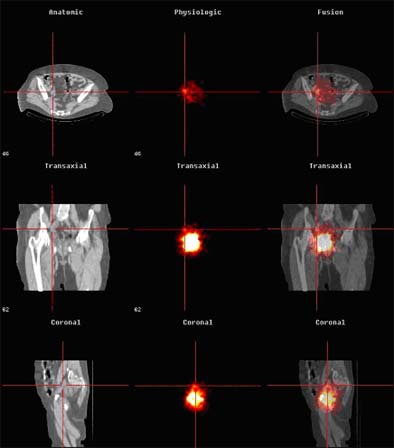

The fusion process, while time-consuming, enabled detailed preoperative evaluation, Sherif said. According to the results, 20 sentinel nodes were detected in 5/6 patients, compared to two sentinel nodes in six patients visualized using planar lymphoscintigraphy alone. Five of six metastatic sentinel nodes in invasive bladder cancer were seen using the fusion protocol, while lymphoscintigraphy detected only 1/6 nodes containing metastases.

| Above, anatomic (CT, left), physiologic (SPECT, middle) and fused images (right) are seen in a bladder cancer patient with sentinel lymph nodes. Images courtesy of Dr. Amir Sherif. |

Overall, planar lymphoscintigraphy alone versus CT-enhanced lymphoscintigraphy detected two and 21 positive nodes, respectively, including 1/2 in patient 1, 0/6 in patient 2, 0/6 in patient 3, 0/4 in patient 4, 1/3 in patient 5, and 0/0 in patient 6, according to the results. Of these, only two positive nodes were detected by the blue dye marker, while the gamma probe detected 10 positive nodes peroperatively. Harvested nodes per patient ranged from six to 24, the total number of detected sentinel nodes per patient ranged from zero to six. All six patients were staged T2.

"The (combined) system is very accurate for localizing the nodes," Sherif said. "Previously we used only planar lymphoscintigraphy with a gamma camera preoperatively, and we had a much lower yield of detected nodes. By using the fused picture with CT/SPECT, we get a much higher yield, first a higher yield of lymph nodes which are considered to be sentinel nodes, and secondly we find anatomical localization (to be) very accurate."